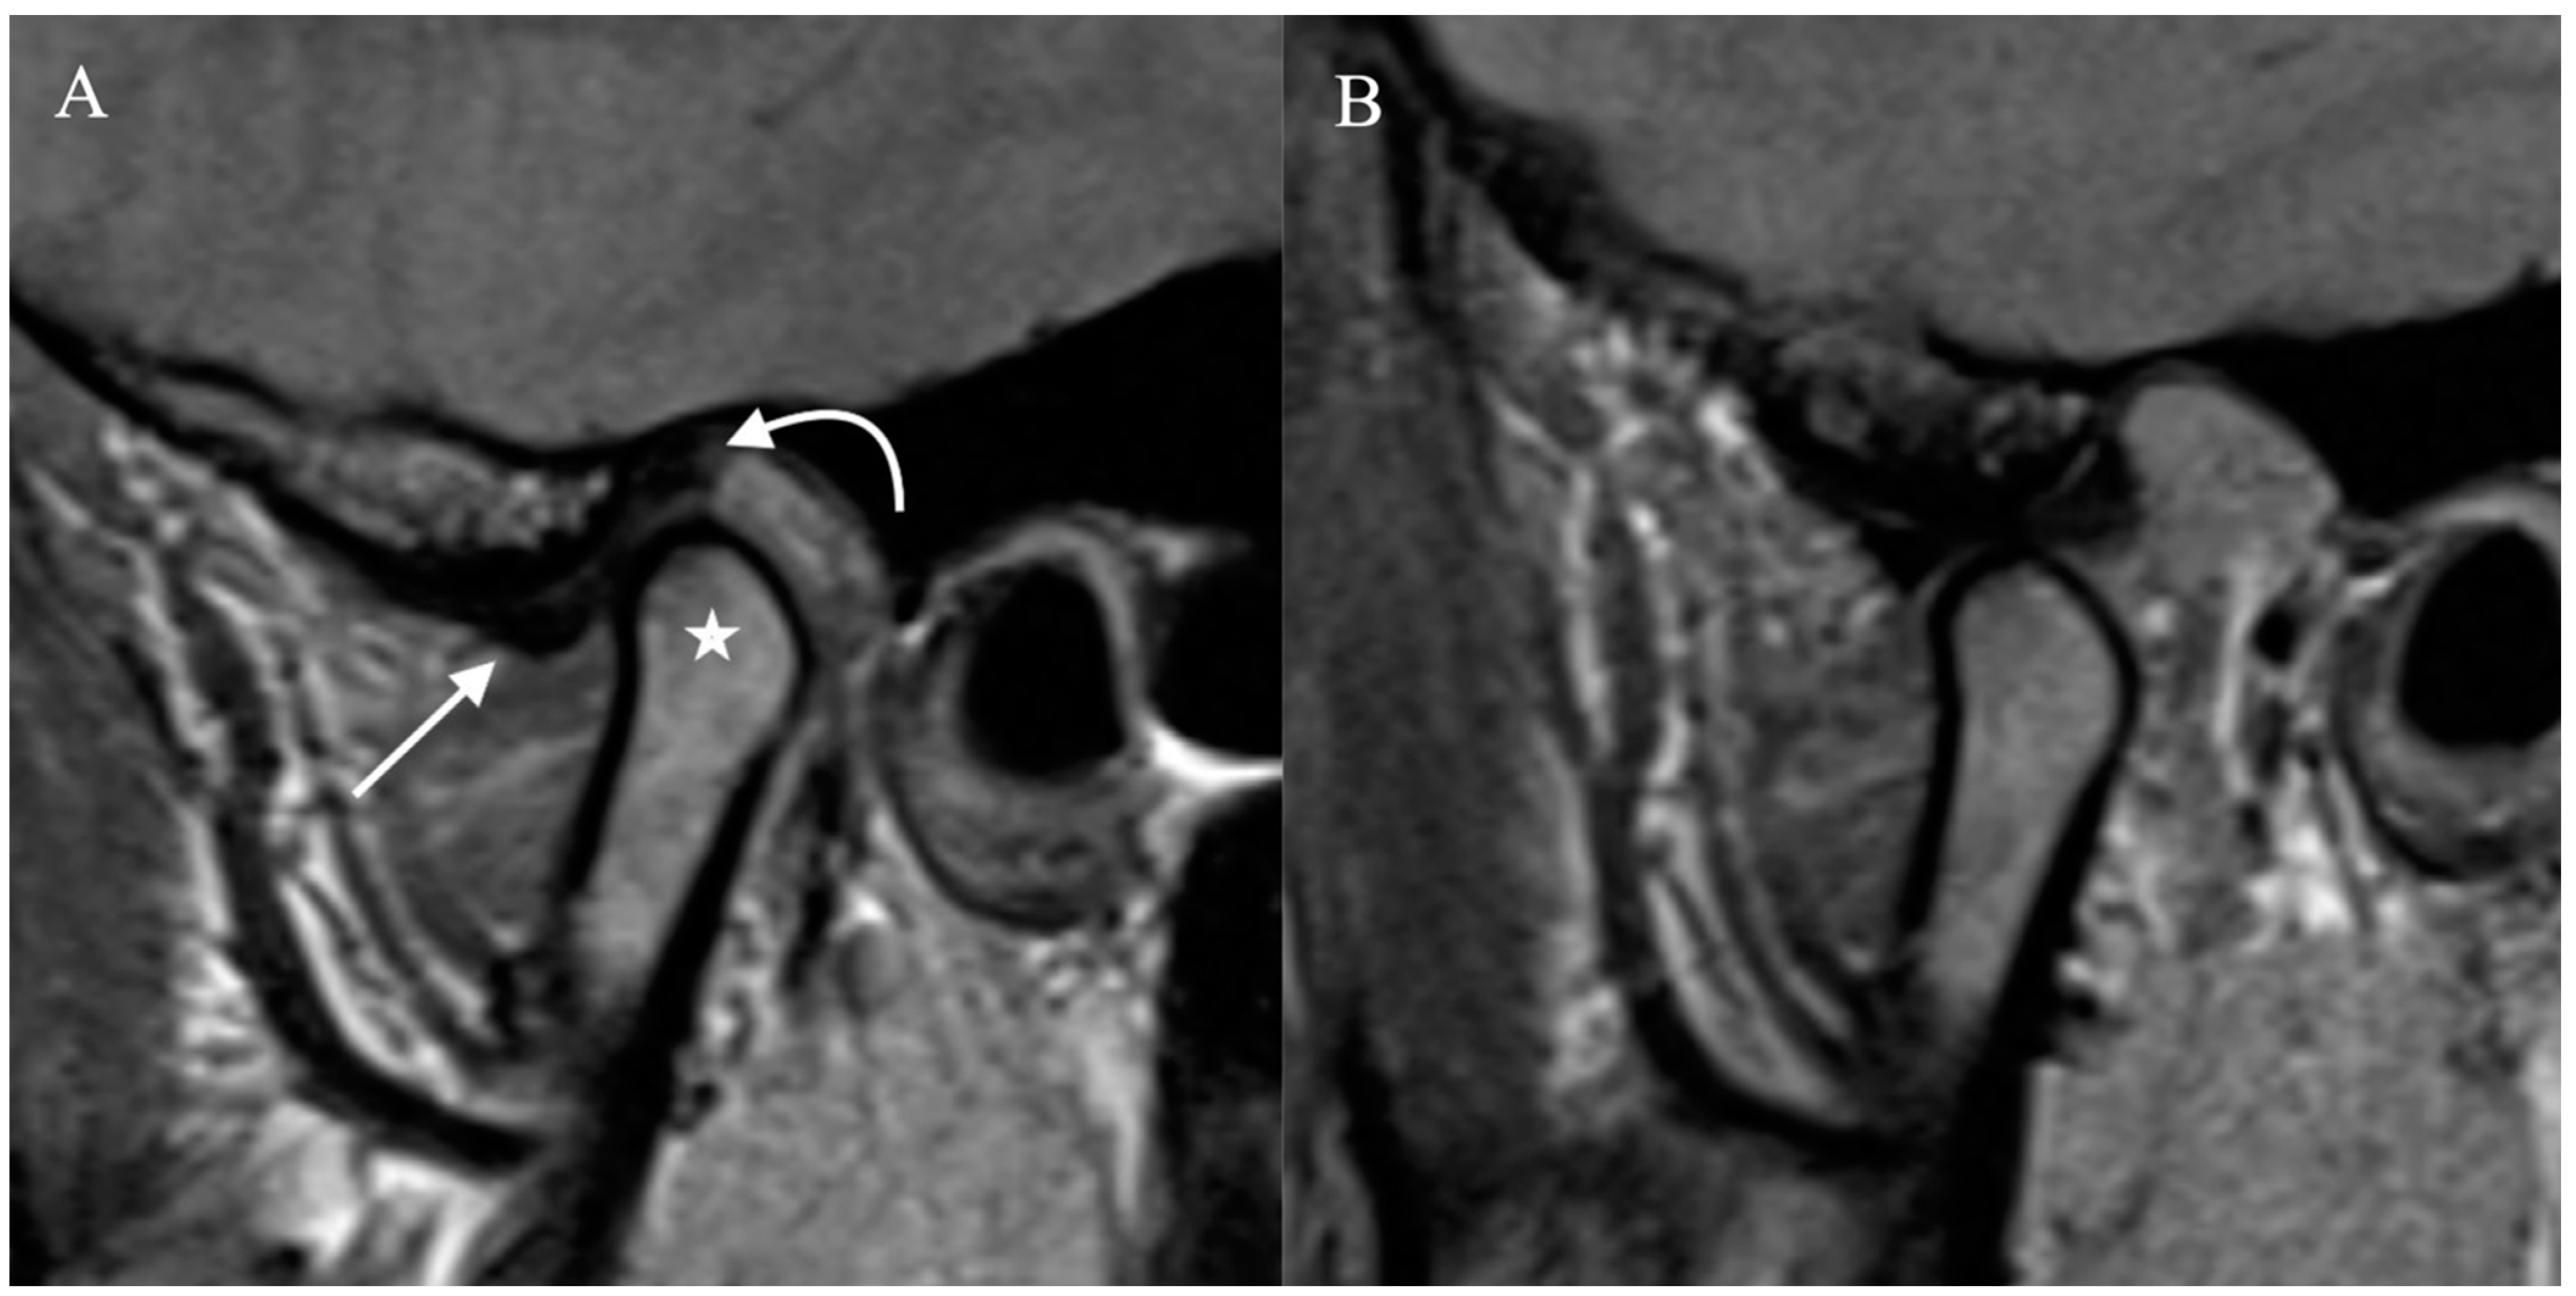

Figure 1. Normal Temporomandibular joint MRI. Proton density sagittal image of the TMJ in closed mouth (A) position shows normal location and bow-tie appearance of the articular disc with anterior (straight arrow) and posterior bands (curved arrow). The mandibular condyle (star) is in an anatomic location within the mandibular fossa. On open mouth images (B), normal condylar rotation and anterior translation are noted.